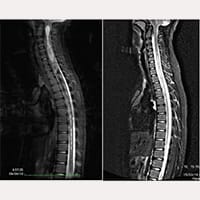

Dall’ottobre del 1993 all’attualità, sono stati in trattamento e operati secondo i protocolli del FILUM-SYSTEM®, più di 2100 pazienti affetti da Sindrome Neuro-Cranio-Vertebrale e/o Malattia del filum con Arnold Chiari I, Siringomielia e Scoliosi, in differenti combinazioni diagnostiche tra le stesse.